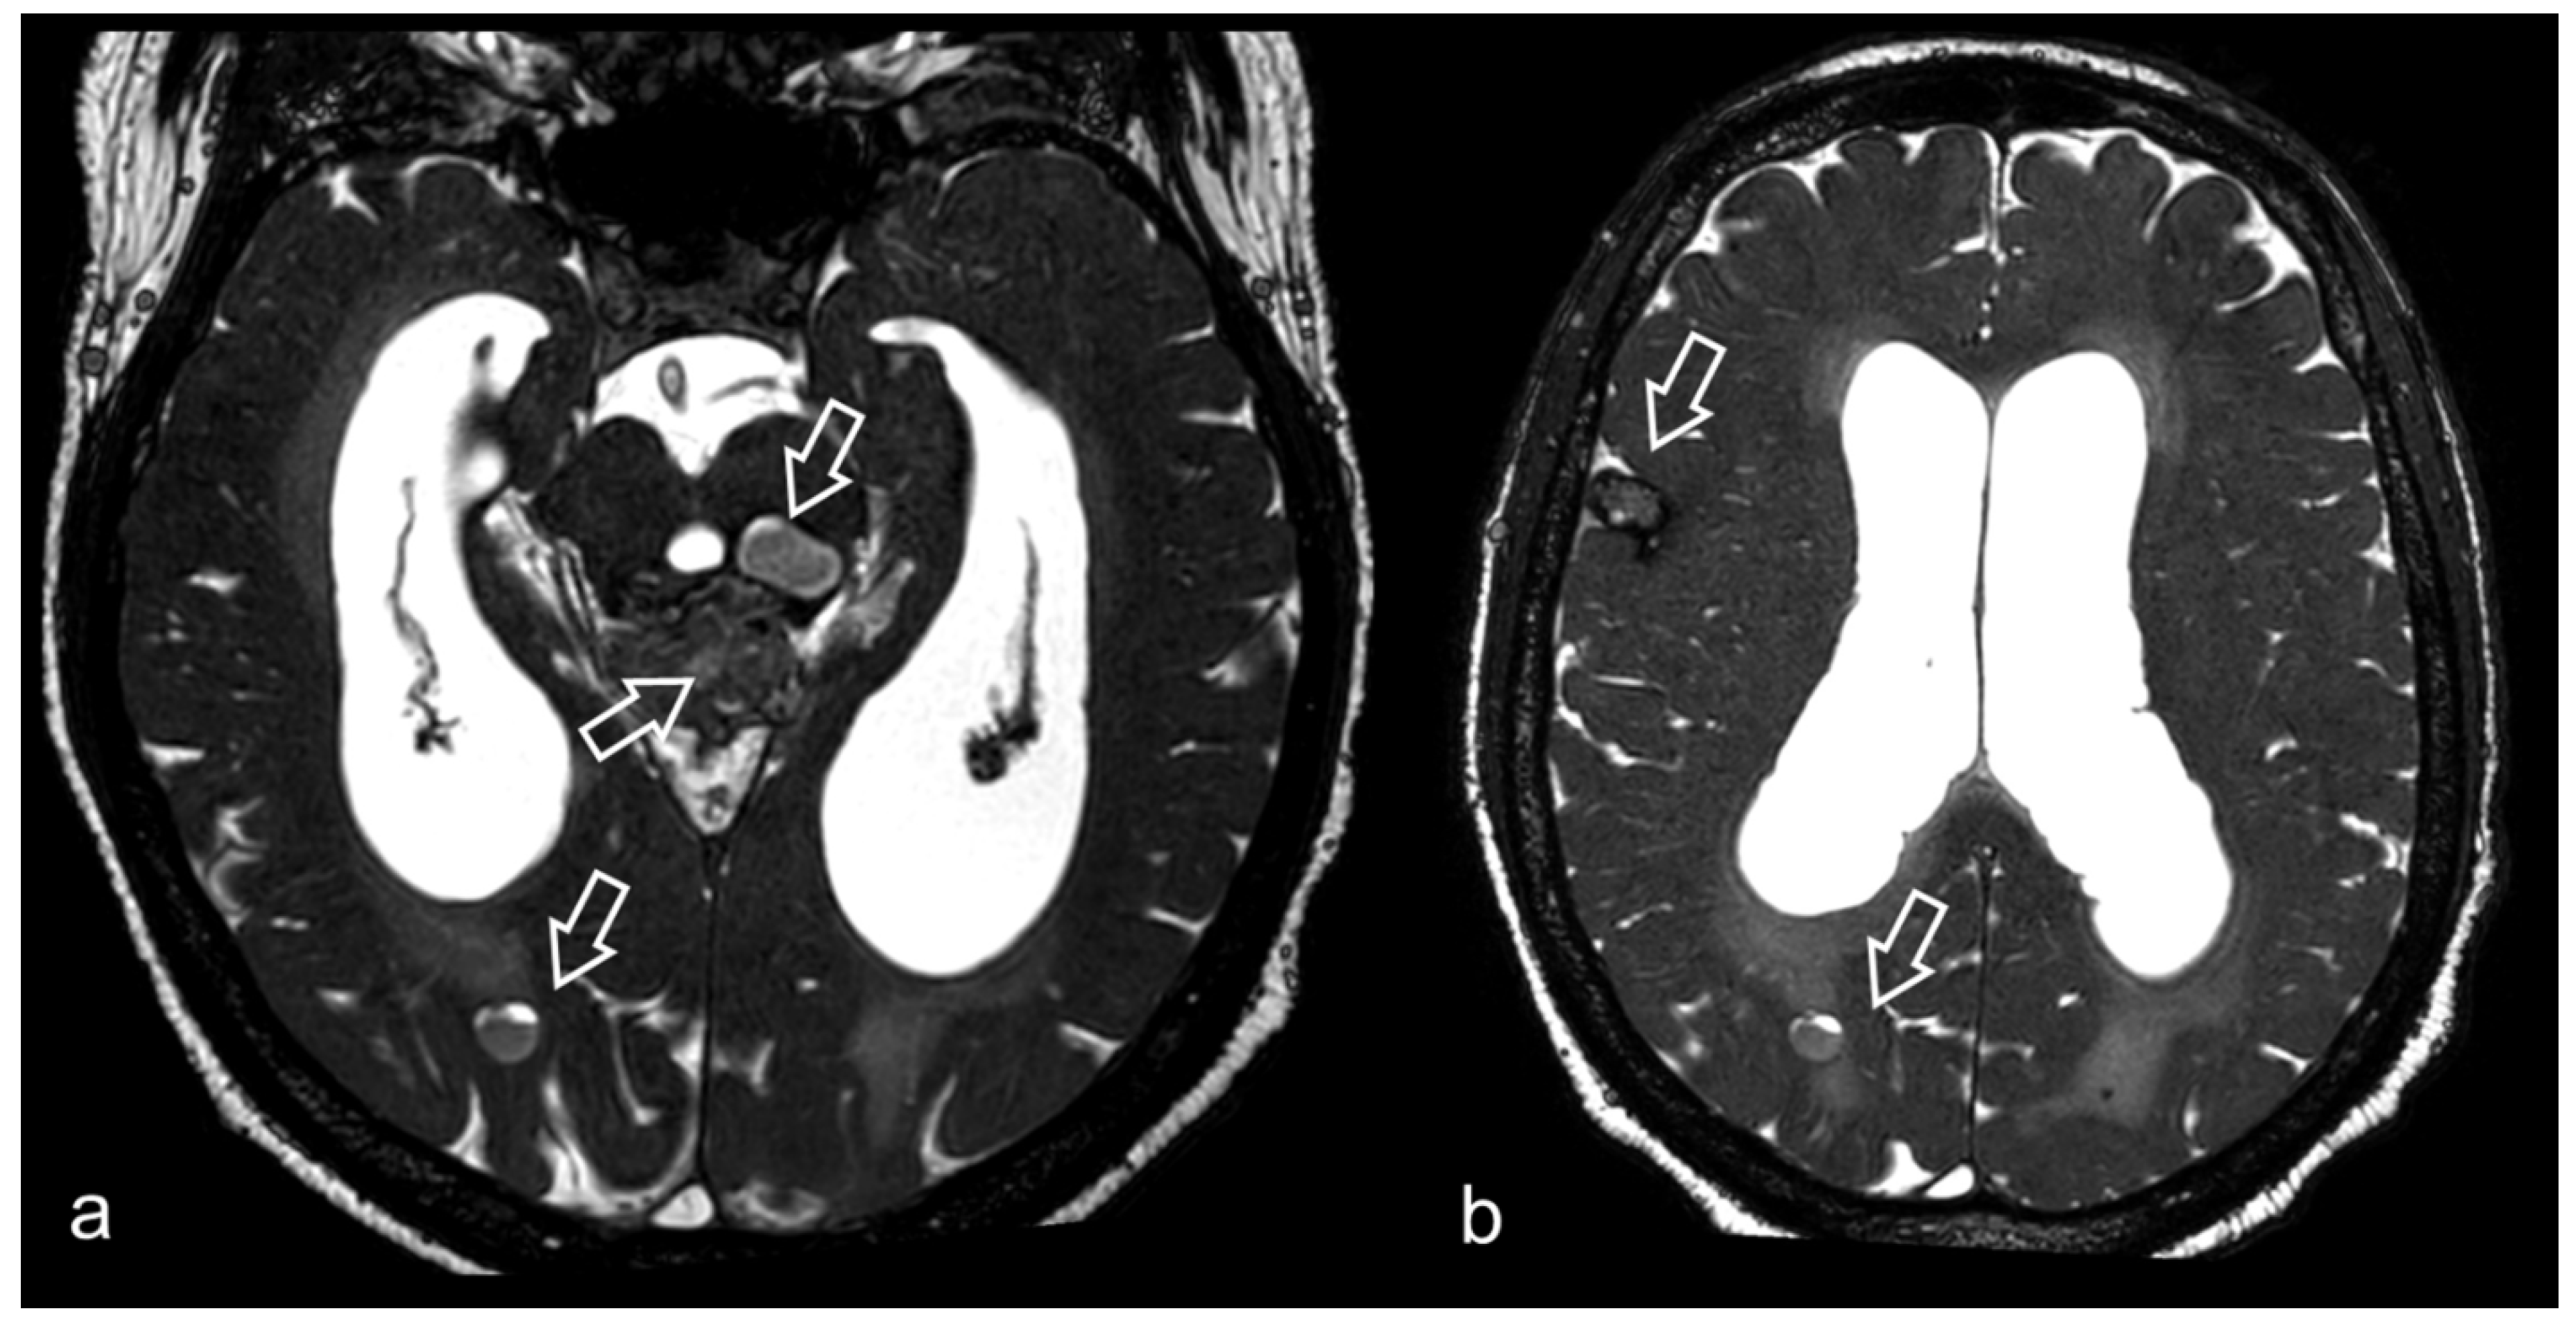

3.5. Hydrocephalus, Ventricular System and Subarachnoid Cisterns

- Kurihara, N.; Takahashi, S.; Tamura, H.; Higano, S.; Furuta, S.; Jokura, H.; Umetsu, A. Investigation of hydrocephalus with three-dimensional constructive interference in steady state MRI. Neuroradiology 2000, 42, 634–638. [Google Scholar] [CrossRef]

- Algin, O.; Hakyemez, B.; Parlak, M. Phase-contrast MRI and 3D-CISS versus contrast-enhanced MR cisternography on the evaluation of the aqueductal stenosis. Neuroradiology 2010, 52, 99–108. [Google Scholar] [CrossRef]

- Shi, J.; Fu, W.; Wu, Q.; Zhang, H.; Zheng, Z.; Zhu, J. Endoscopic third ventriculostomy associated 3D-construcive inference steady state MRI for obstructed hydrocephalus: A retrospective study. Clin. Neurol. Neurosurg. 2013, 115, 896–901. [Google Scholar] [CrossRef] [PubMed]

- Da Costa Val Filho, J.A.; da Silva Gusmão, S.N.; Furtado, L.M.F.; de Macedo Machado Filho, G.; Maciel, F.L.A. The role of the Liliequist membrane in the third ventriculostomy. Neurosurg. Rev. 2021, 44, 3375–3385. [Google Scholar] [CrossRef] [PubMed]

- Fushimi, Y.; Miki, Y.; Ueba, T.; Kanagaki, M.; Takahashi, T.; Yamamoto, A.; Haque, T.L.; Konishi, J.; Takahashi, J.A.; Hashimoto, N.; et al. Liliequist membrane: Three-dimensional constructive interference in steady state MR imaging. Radiology 2003, 229, 360–365, discussion 365. [Google Scholar] [CrossRef] [PubMed]